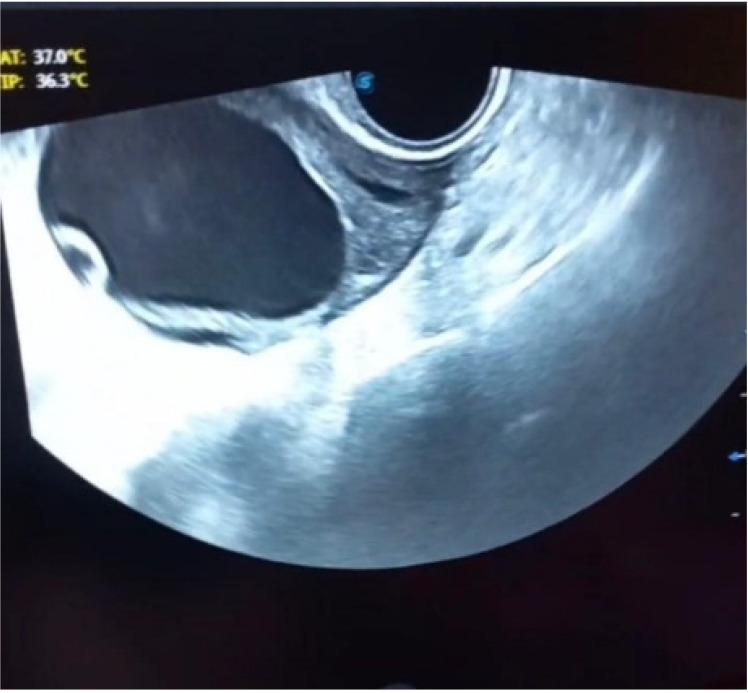

Case presentation: A 47-year-old woman with chronic abdominal pain and left hemipelvic fullness was referred to the Obstetrics Clinic of the Kowsar Hospital of Qazvin. Abdominopelvic sonography revealed a cystic mass, which primarily suggested a cyst adenoma. The tumor marker levels were within normal limits. After surgical resection, histopathological examination showed a cystic mass with dimensions of 10×6×3 cm, smooth external and internal aspects, wall thickness of 0.3 cm, and multiple pieces of irregular gray membranous tissue. The patient was treated with albendazole 3 months after surgery, and a 6-month follow-up sonogram revealed no signs of recurrence.